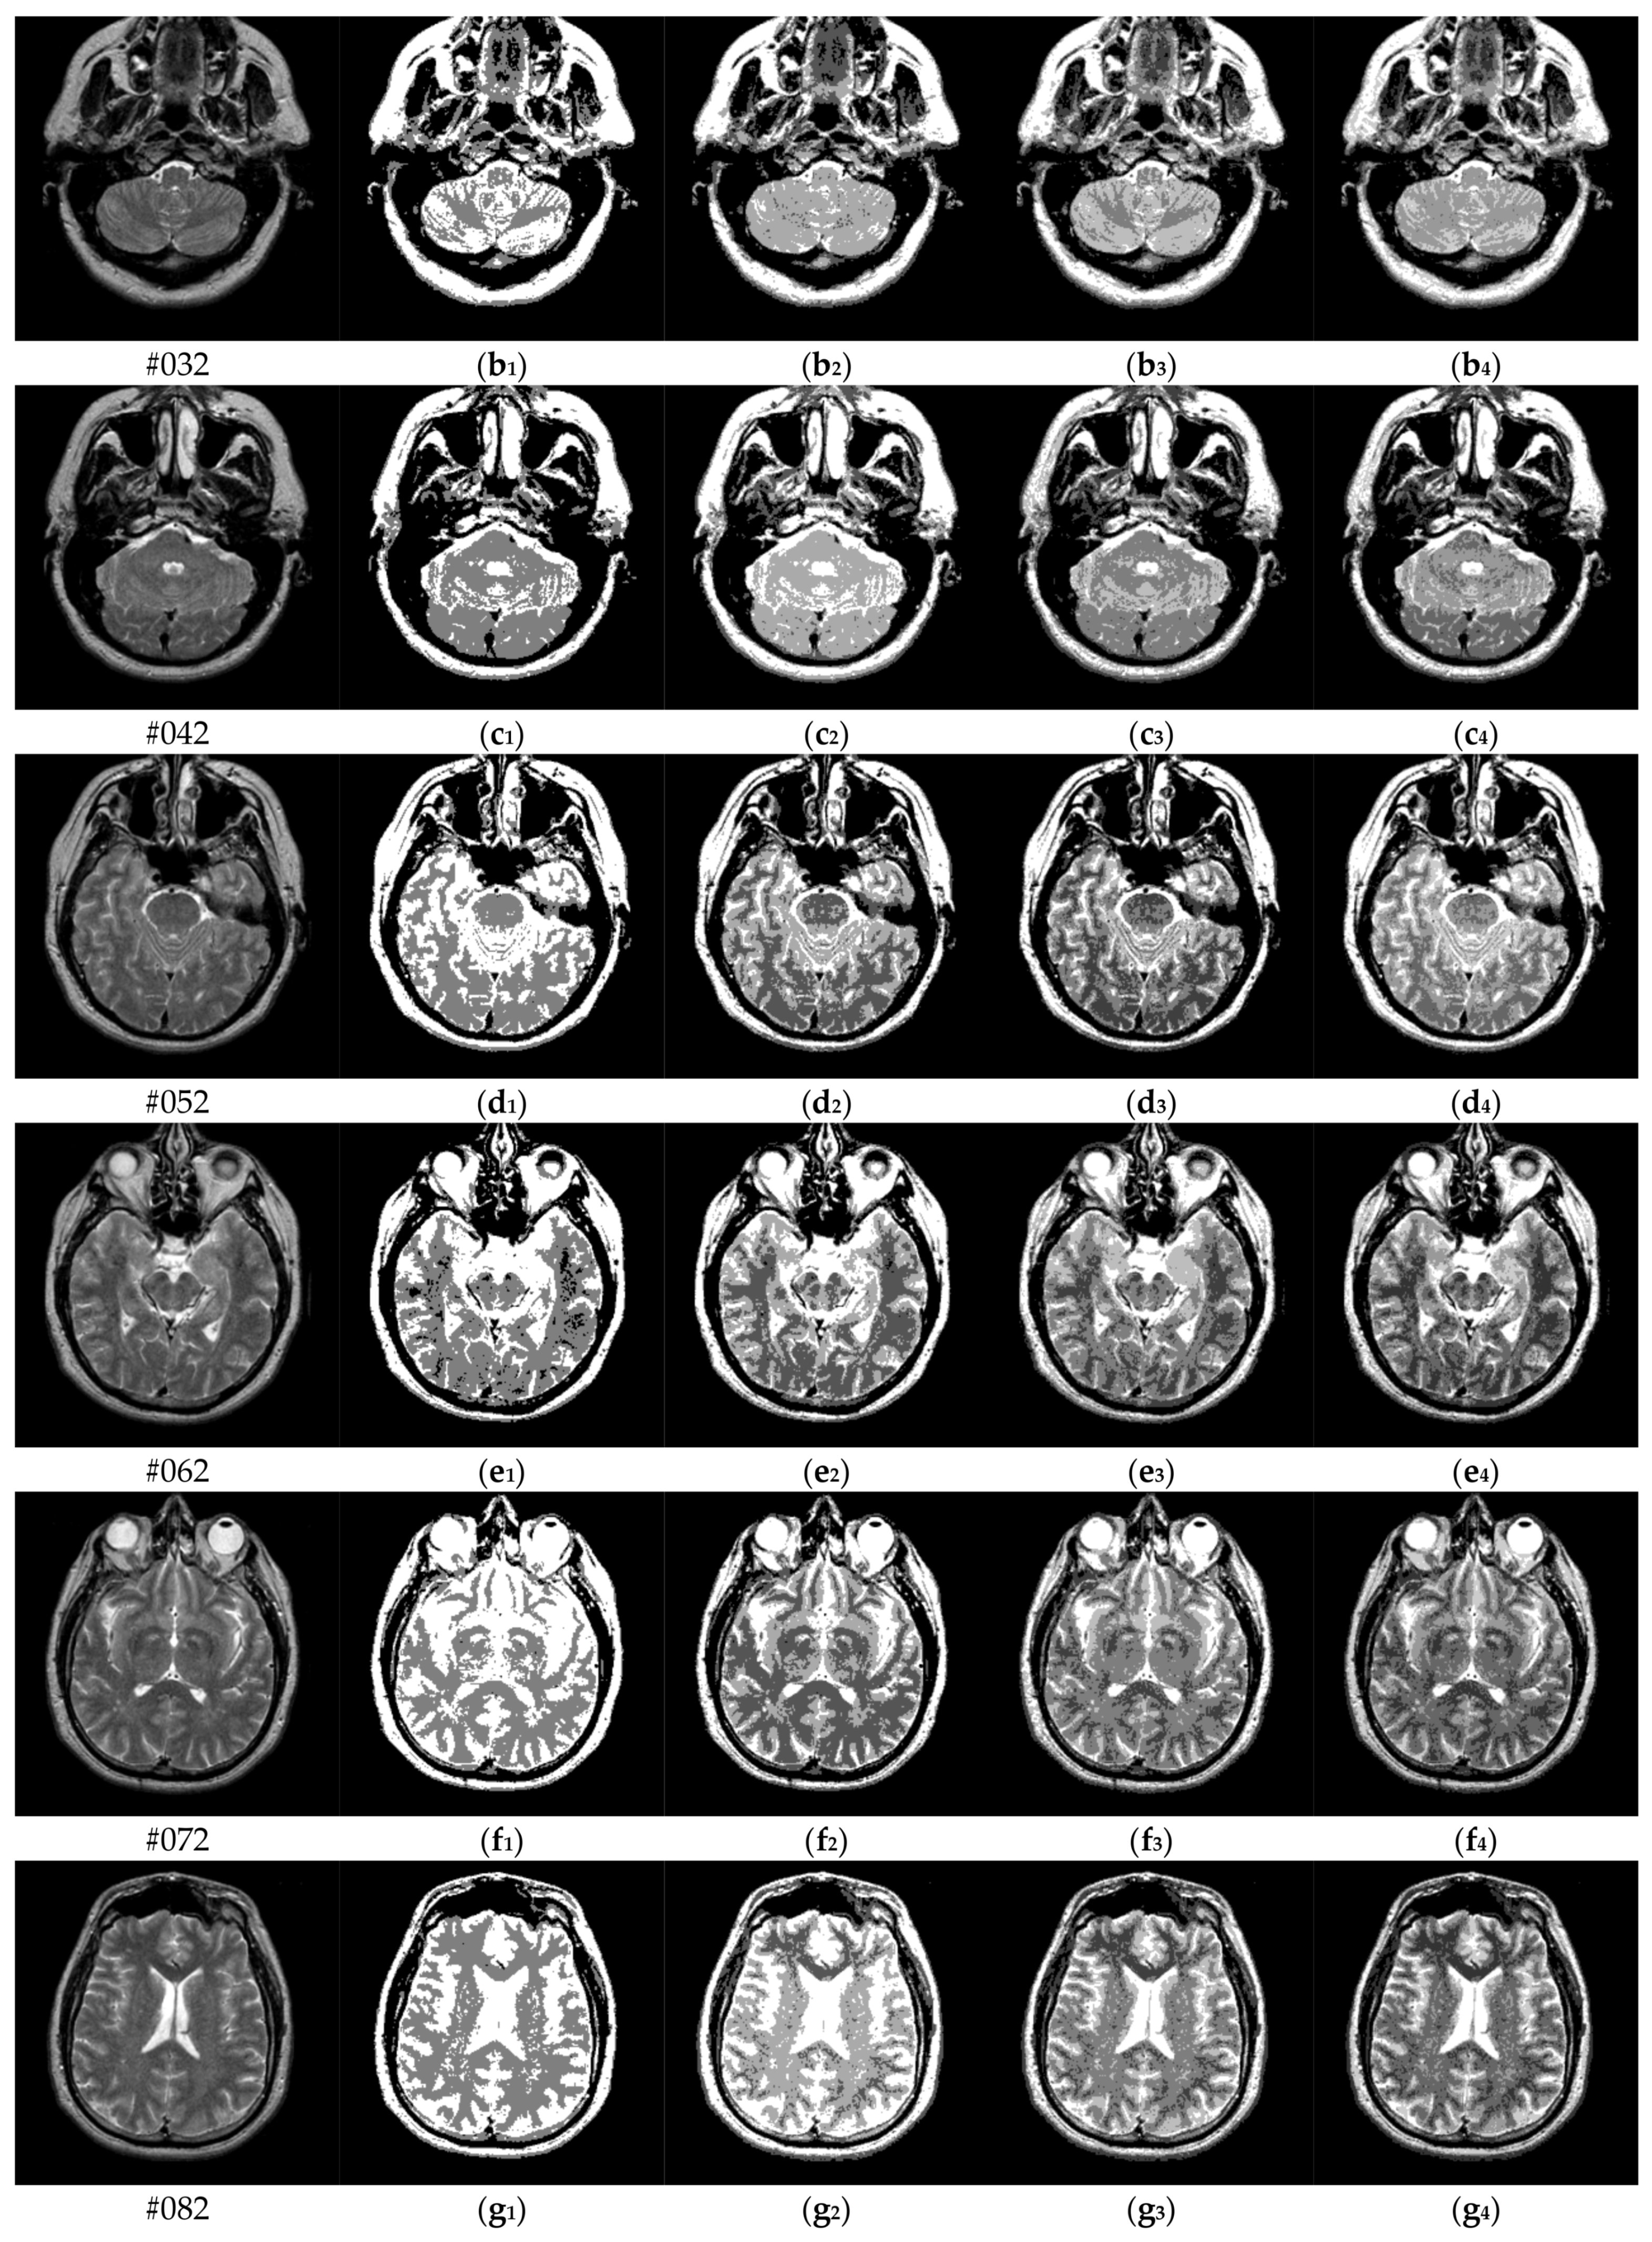

To verify the performance of the proposed algorithm, five representative multi-threshold segmentation algorithms are selected for comparative experiments. The five comparative experimental algorithms are: (1) image threshold segmentation algorithm based on particle swarm optimization (PSO), (2) image threshold segmentation algorithm based on bacterial foraging (BF), (3) image threshold segmentation algorithm based on adaptive bacterial foraging (ABF), (4) image threshold segmentation algorithm based on Nelder-Mead simplex (NMS), (5) image multi-threshold segmentation algorithm based on real coded genetic algorithm (RCGA) [43]. The number of thresholds is set to K = 2, 3, 4, and 5, respectively. Due to the limited space, we only show the segmentation results of the proposed algorithm in this paper. Figure 8 shows the segmentation results of Slice#022~#112 when the threshold K = 2, 3, 4, 5. Intuitively, the proposed algorithm can better segment each region of the experimental image, and the continuity of different regions is well guaranteed. At the same time, the visual effects are satisfactory.

Figure 8.

Segmentation results obtained by the proposed algorithm for brain slices #022~#112; (a1–j1) display the results of 2-thresholding; (a2–j2) display the results of 3-thresholding; and (a3–j3) display the results of 4-thresholding; (a4–j4) display the results of 5-thresholding.